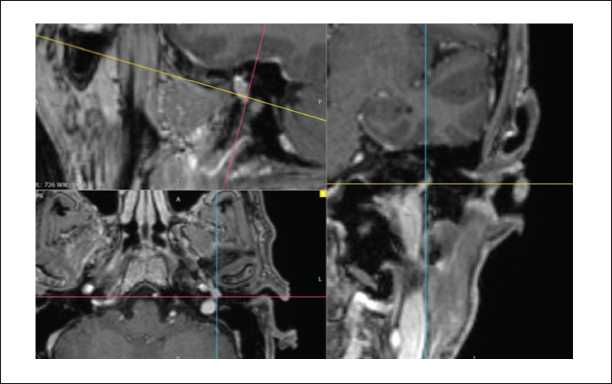

На МРТ головного мозга и мягких тканей шеи определялось распространение образования на капсулу улитки и на область правой мостомозжечковой цистерны (рисунки 6, 8, 9). Соответствующие отделы головного мозга не изменены. Определялись признаки распространения процесса по ходу внутренней яремной вены (1). Просвет внутренней яремной вены в этой области не прослеживался (2) (рисунок 7).

Рисунок 6. МРТ головного мозга и мягких тканей шеи, Т2-ВИ с подавлением сигнала от жировой ткани, в корональной плоскости. Параганглиома, тип С: определяется распространение образования на капсулу улитки.

Рисунок 7. МРТ головного мозга и мягких тканей шеи, Т2-ВИс подавлением сигнала от жировой ткани, в корональной плоскости. Параганглиома, тип С: определяются признаки распространения процесса по ходу внутренней яремной вены каудально до уровня С2, с размером экстракраниального компонента 50х18 мм (1). Просвет внутренней яремной веныв этой области не прослеживается (2), субстенотические отделы существенно не расширены.

Рисунок 8. МРТ головного мозга и мягких тканей шеи, Т2-ВИс подавлением сигнала от жировой ткани, в корональной плоскости. Параганглиома, тип С. Послеоперационный контроль спустя 6 месяцев после хирургического лечения: данныхза рецидив новообразования не выявлено.

Рисунок 9. МРТ головного мозга и мягких тканей шеив аксиальной проекции, Т2-ВИ с подавлением сигналаот жировой ткани, в аксиальной плоскости. Параганглиома, тип С. Послеоперационный контроль спустя 6 месяцев после хирургического лечения: данных за рецидив новообразованияне выявлено.

Инфратемпоральный доступ [4, 14, 15, 16, 17, 18] применен у 8 пациентов c опухолью типа C3. Ввиду распространения новообразования в просвет яремной вены осуществлялась перевязка яремной вены на уровне позвонка С1 за задней ножкой двубрюшной мышцы в области ее прикрепления. В ходе операции лицевой нерв был деканализирован от шилососцевидного отверстия до коленчатого ганглия и выполнялась его транспозиция кпереди. Во всех случаях медиальная и нижняя поверхности мастоидального сегмента лицевого нерва были интимно спаяны с опухолевой тканью. Далее скелетизировали, вскрывали и облитерировали сигмовидный синус, опухоль удалялась вместе с луковицей яремной вены. Интраоперационно с помощью электромагнитной навигационной системы удалось сравнить и сопоставить полученную с помощью МРТ и КТ картину распространения процесса (рисунки 5, 6, 7, 8, 9). Под контролем навигации выполнялось удаление фрагментов опухоли со стенок внутренней сонной артерии. После удаления опухоли и гемостаза лицевой нерв отграничивался аутофасцией, послеоперационная полость облитерировалась аутожиром с передней брюшной стенки. Слуховой проход ушивался по типу «слепого мешка».